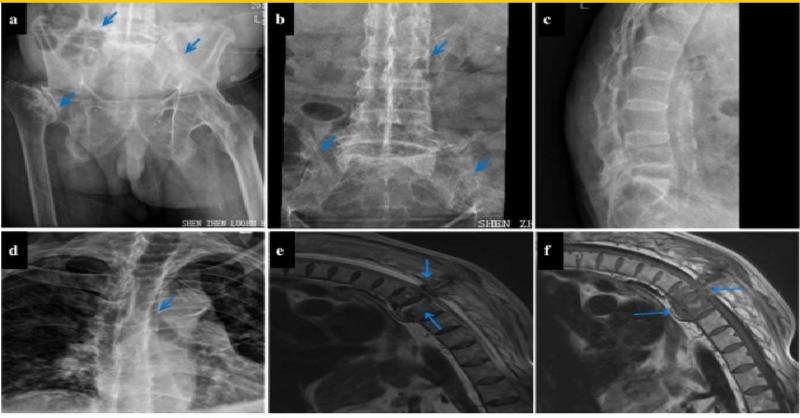

Atraumatic Thoracic Spinal Fracture mimicking Herpes Zoster Neuralgia: A case report

Intercostal neuralgia is most prevalent in herpes zoster patients, but it could also be the first sign of a serious illness, such as an atraumatic spinal fracture, which can have fatal repercussions if not recognized and treated early. Intercostal neuralgia tends to cause thoracic pain, which affects your chest wall and upper trunk. Background: Int